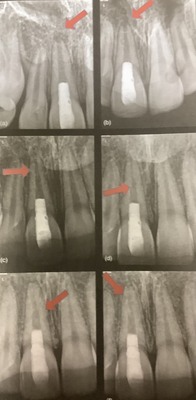

⚪︎上の方を真っ直ぐにする。

根っこの先まで無理なく器具が入るためにです。

上手なアクセスによって、神経の管が変な方向に削れたり、器具が折れたりするのを防げます。